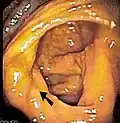

Cecum

Imagine endoscopică a cecumului, săgeata arătând către valva ilocecală